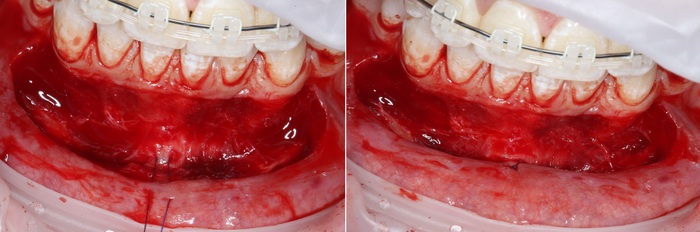

2 – проведение пластики десны.

Был взят трансплантат в области бугра верхней челюсти (это то место, где раньше был зуб мудрости).

Далее проведена пластика десны, снова два месяца ожиданий и установка временной коронки: